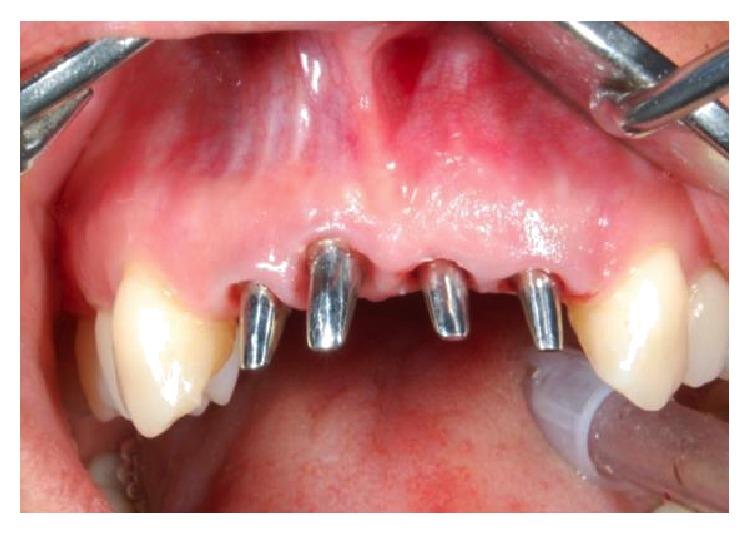

The functional and aesthetic restoration of teeth compromised due to aggressive periodontitis presents numerous challenges for the clinician. Horizontal bone loss and soft tissue destruction resulting from periodontitis can impede implant placement and the regeneration of an aesthetically pleasing gingival smile line, often requiring bone augmentation and mucogingival surgery, respectively. Conservative approaches to the treatment of aggressive periodontitis (i.e., treatments that use minimally invasive tools and techniques) have been purported to yield positive outcomes. Here, we report on the treatment and five-year follow-up of patient suffering from aggressive periodontitis using a minimally invasive surgical technique and implant system. By using the methods described herein, we were able to achieve the immediate aesthetic and functional restoration of the maxillary incisors in a case that would otherwise require bone augmentation and extensive mucogingival surgery. This technique represents a conservative and efficacious alternative to the aesthetic and functional replacement of teeth compromised due to aggressive periodontitis.

侵袭性牙周炎导致牙齿功能和美观受损,给临床医生带来诸多挑战。牙周炎引起的水平骨吸收和软组织破坏会妨碍种植体植入以及美观的牙龈微笑线的再生,通常分别需要进行骨增量和膜龈手术。据称,侵袭性牙周炎的保守治疗方法(即使用微创工具和技术的治疗方法)能产生积极效果。在此,我们报告了一名侵袭性牙周炎患者采用微创外科技术和种植系统的治疗及五年随访情况。通过使用本文所述方法,在原本需要骨增量和广泛膜龈手术的病例中,我们成功实现了上颌切牙的即刻美观和功能恢复。该技术是侵袭性牙周炎导致牙齿功能和美观受损时,一种保守且有效的替代治疗方法。